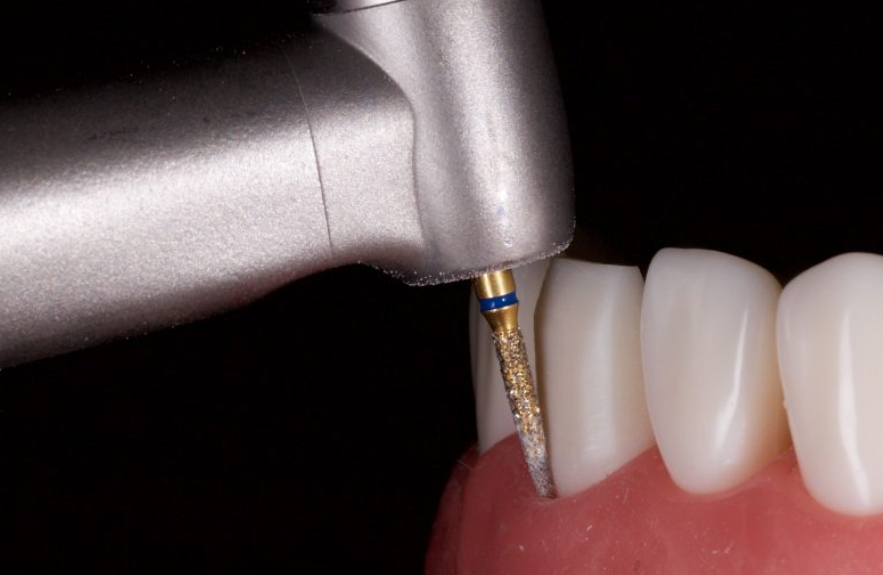

그래서 선택한 방식이 BOPT(Biologically Oriented Preparation Technique) 크라운이에요.

BOPT란?

☑️ 경계선을 깊게 만들지 않고 치아의 바깥 라인만 아주 살짝 정리

☑️ '최소량만' 다듬는 방식

마모가 심해도 치아를 최대한 지키면서 크라운을 만들 수 있는 기법이에요.

필요한 양만 다듬어서 치아 색상을 확인했습니다.

촬영일 : 251020